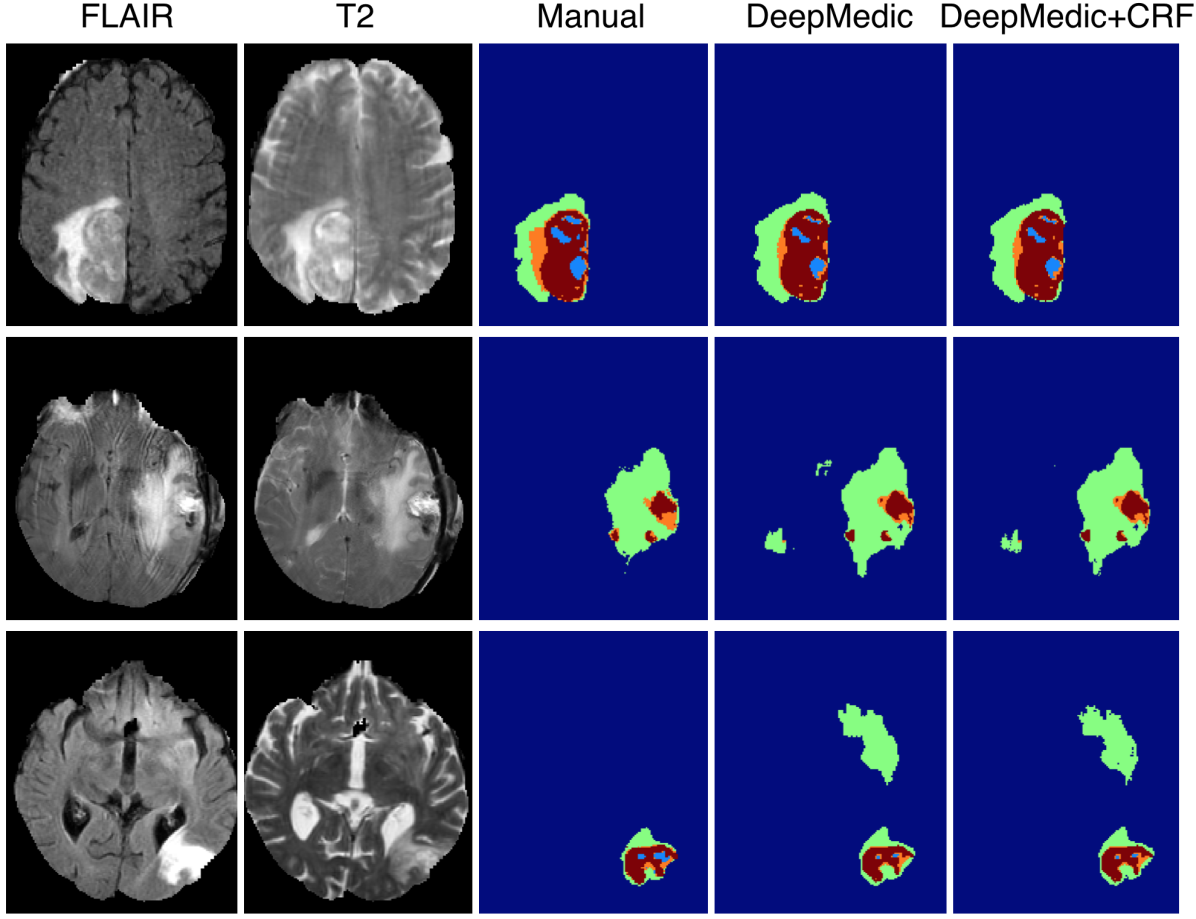

Quantitative results from the application of the DeepMedic, the CRF and an ensemble of three similar networks on the training data are presented in Table 2. The latter two offer an improvement, albeit fairly small since the performance of DeepMedic is already rather high in this task. Also shown are results from previous works, as reported on the online evaluation platform. Various settings may vary among submissions, such as the pre-processing pipeline or the number of folds used for cross-validation. Still it appears that our system performs favourably compared to previous state-of-the-art, including the semi-automatic system of Bakas et al. (2015) (bakas1) who won the latest challenge and the method of Pereira et al. (2015) (peres1), which is based on grade-specific 2D CNNs and requires visual inspection of the tumor and identification of the grade by the user prior to segmentation. Examples of segmentations obtained with our method are shown in Fig. 12. DeepMedic behaves very well in preserving the hierarchical structure of the tumor, which we account to the large context processed by our multi-scale network.